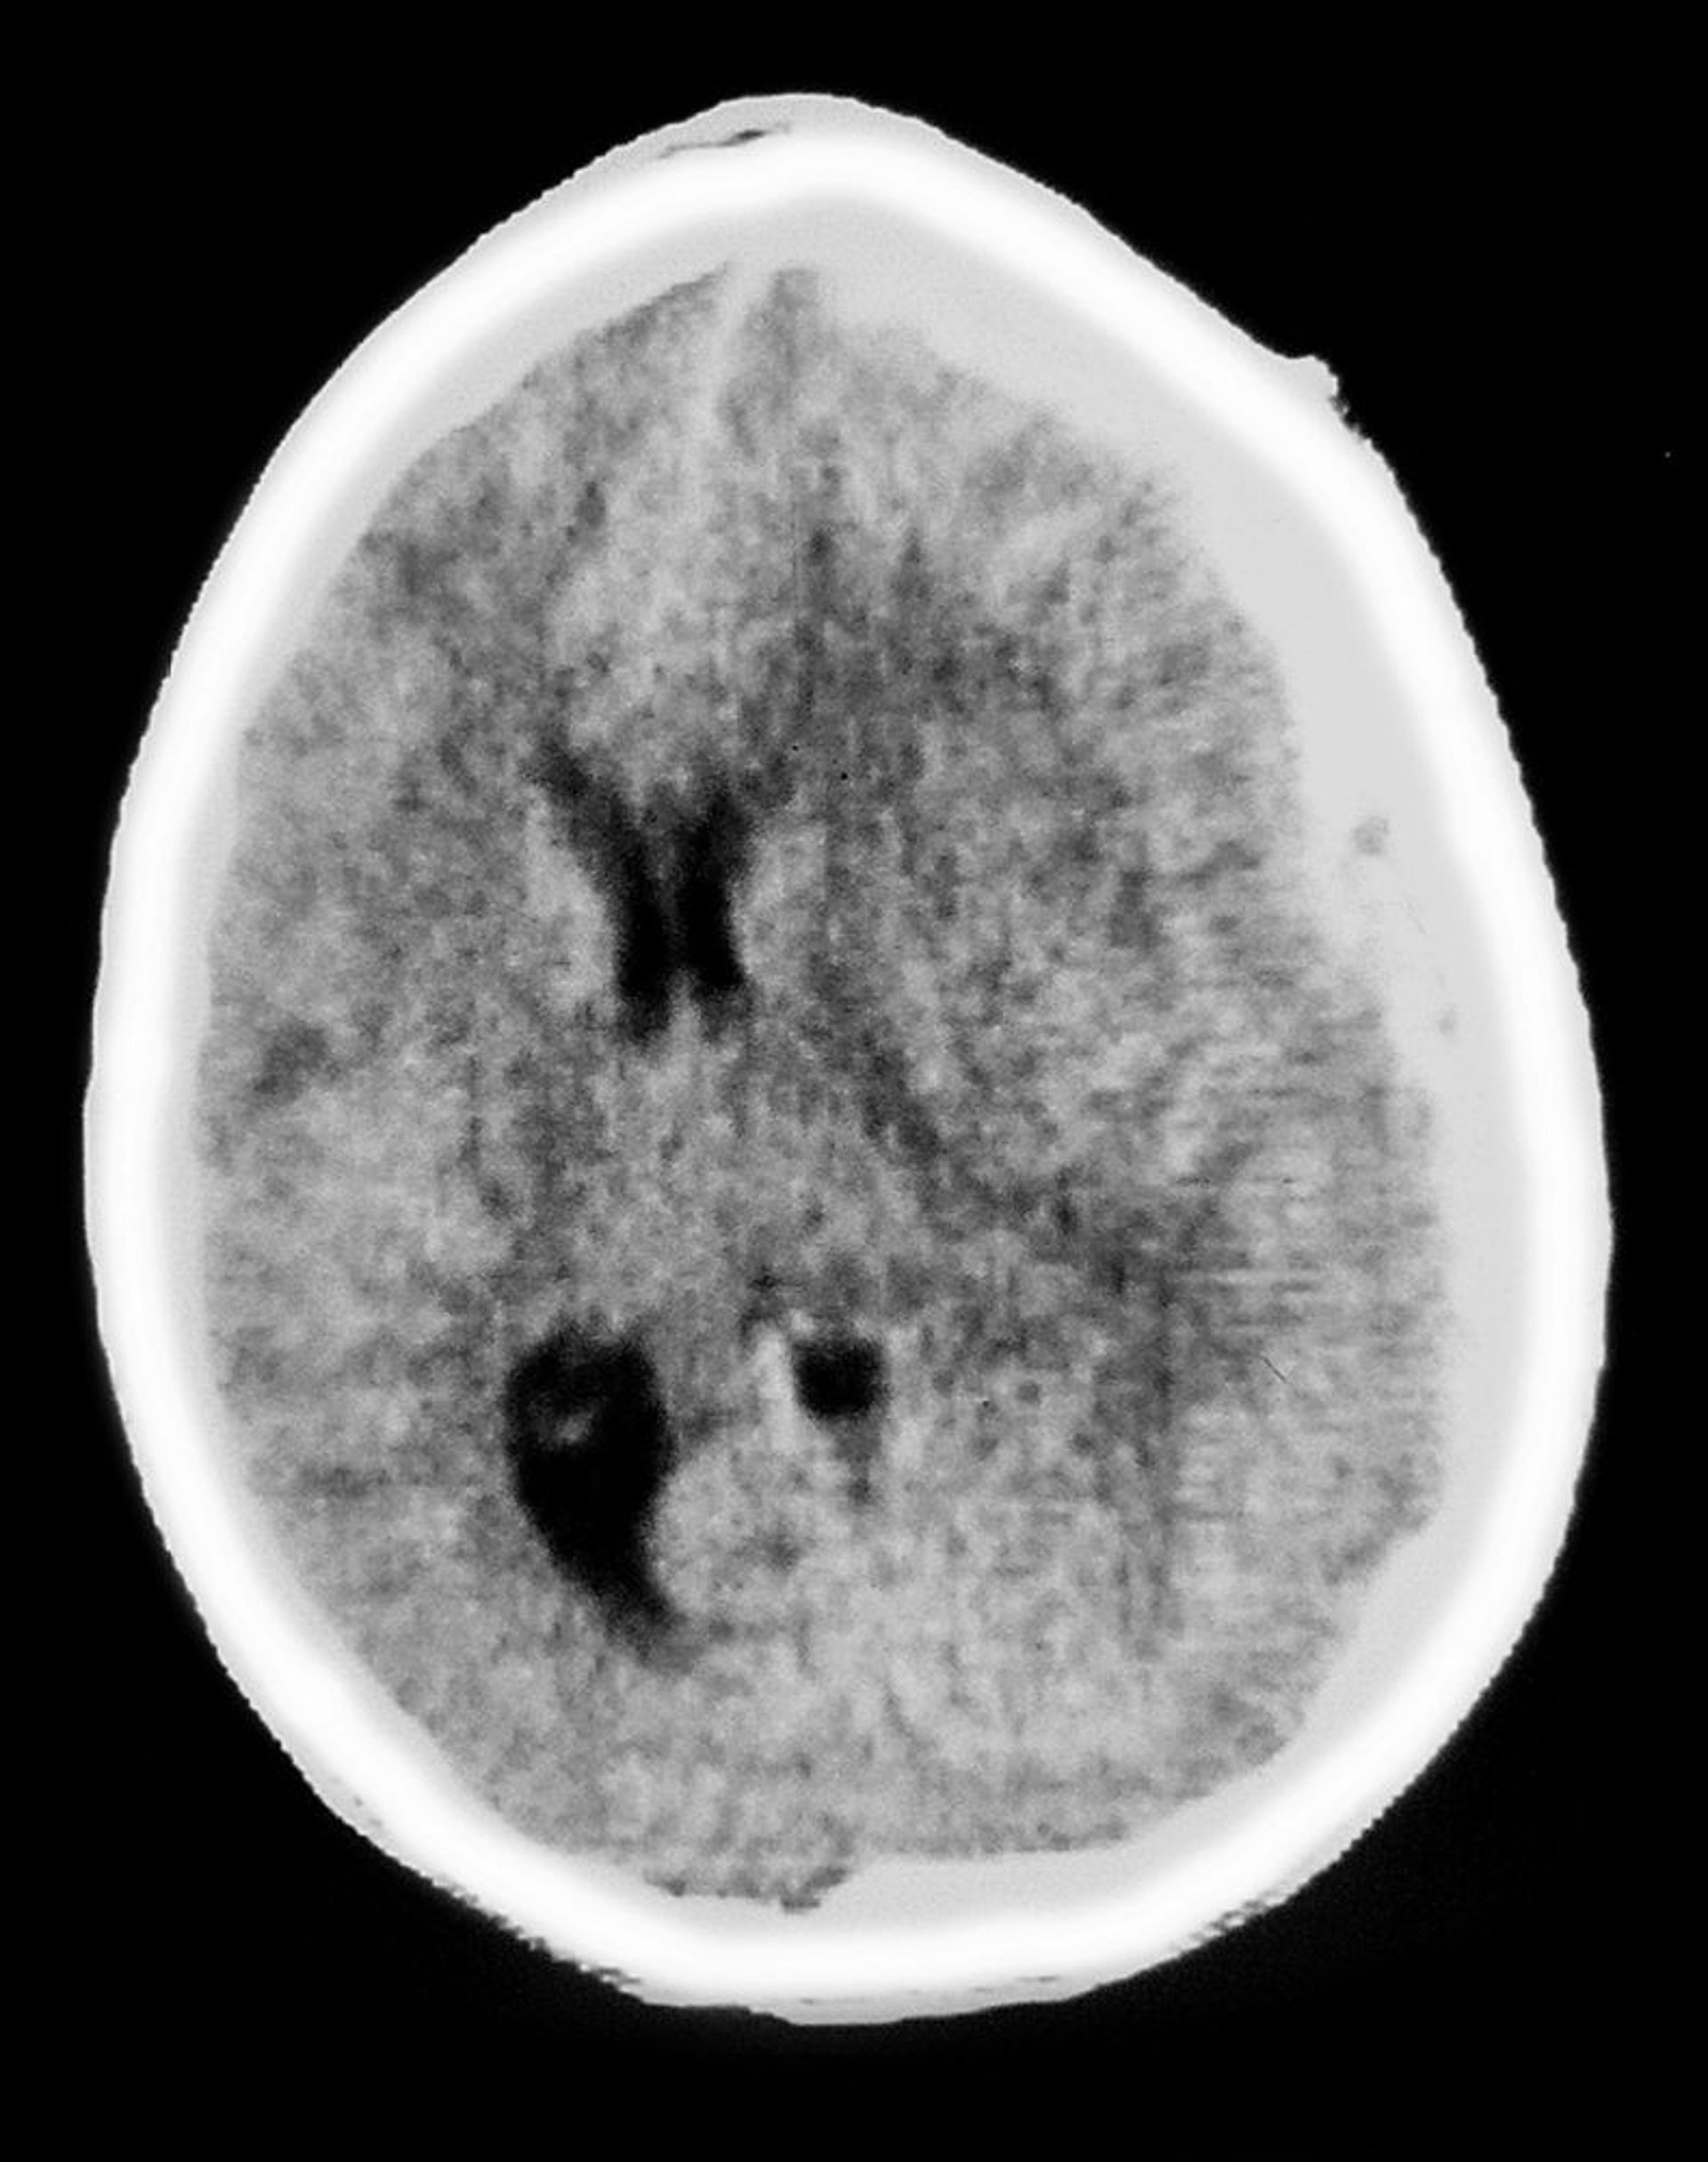

Hematoma subdural

Esta TC muestra una opacidad en forma de medialuna sobre el tejido encefálico, característica de un hematoma subdural. También puede ocurrir un efecto de masa, con compresión ventricular y desplazamiento de la línea media.